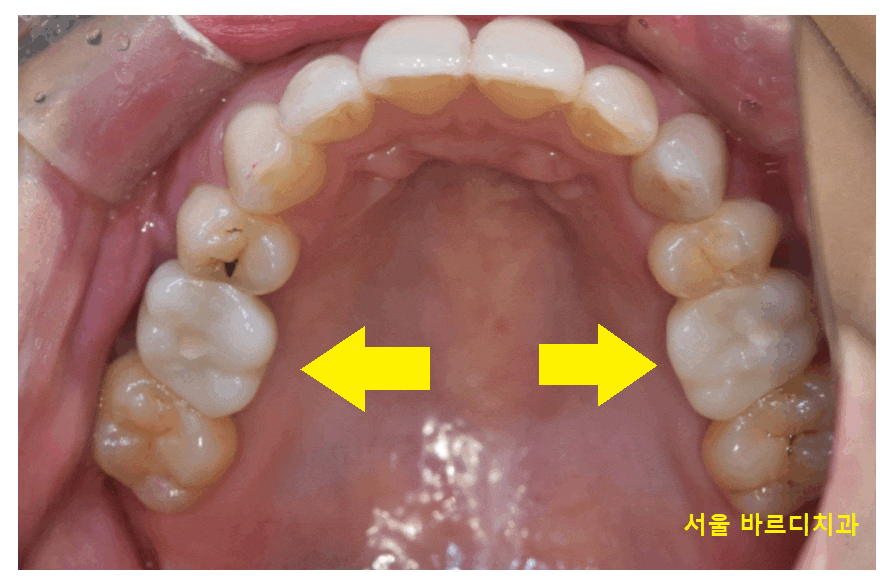

윗니 어금니의 경우 양쪽 모두

충치가 진행되어 뿌리만 남을정도로 썩었습니다.

아래 치아에도 충치가 있긴 했지만

윗니 어금니에 비해서는 상황이 좋은편이었습니다.

23.12.30

특징적인 것으로는

모두 제 1큰 어금니가 썩으셨네요~